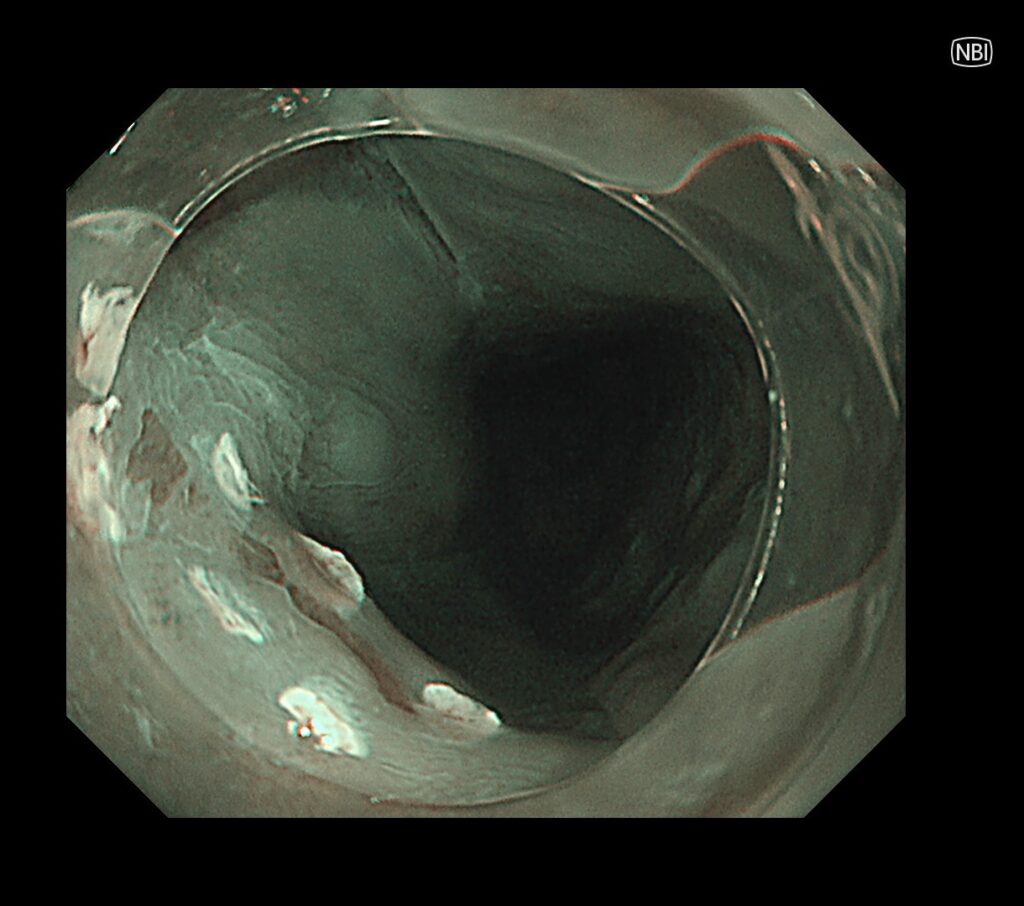

近傍に癌を疑う所見を認め、拡大観察可能な内視鏡に切り替え、再度観察。

NBI拡大モードで癌血管を視認。